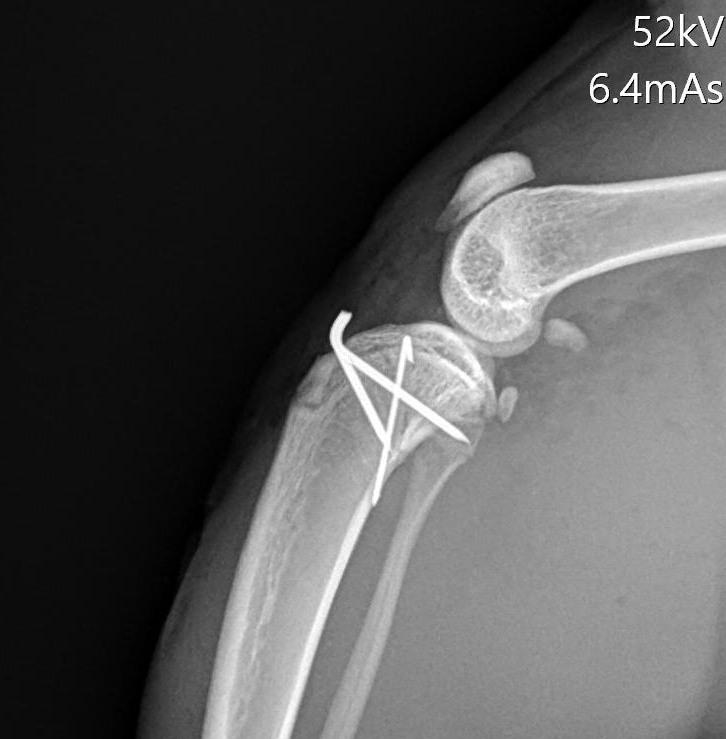

我們練習一下: 第一張照片R是正常的膝蓋, 找找看標記L的第二張 部分哪裡飛起來了呢?

後面兩張就是骨科醫師用骨釘(亮亮一根根) 把骨頭回復到原本該在的位置, 大部分狗狗貓貓都能在3-5天後很好的使用受傷的腳~